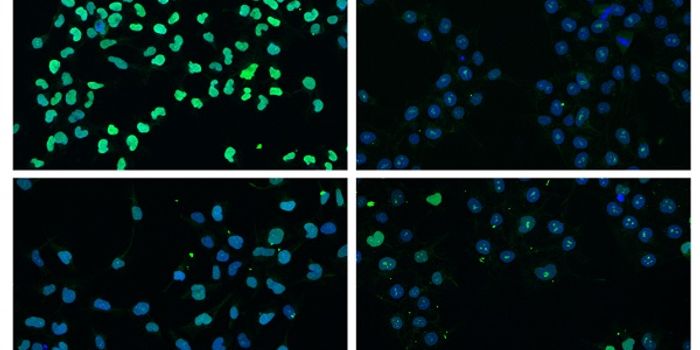

SEP 07, 2016CancerWhen treating cancer, doctors have turned to immunotherapy to help target actual tumors instead of attacking all rapidly ...